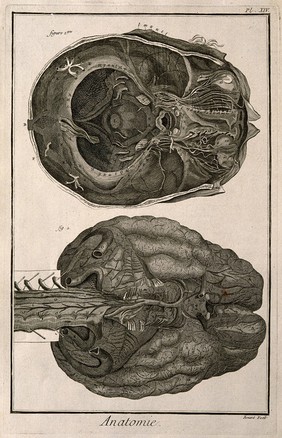

The anatomy of the brain : containing its mechanism and physiology : together with some new discoveries and corrections of ancient and modern authors upon that subject : to which is annex'd a particular account of animal functions and muscular motion : the whole illustrated with elegant sculptures after the life by H. Ridley.

Ridley, Humphrey, 1653-1708Date: 1695

The brain, after Haller and Ridley. Engraving by Prevost, 1762.

The brain, after Haller and Ridley. Engraving, 18th century.

The brain, after Haller and Ridley. Engraving by Benard, late 18th century.